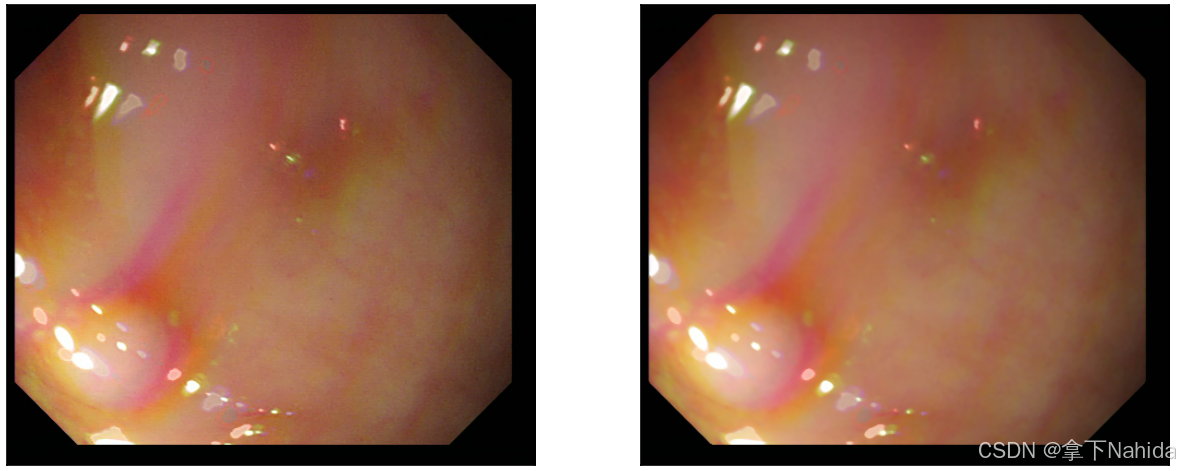

a.均值滤波

均值滤波是最简单的线性平滑滤波方法,它通过计算窗口内所有像素的平均值来代替中心像素的值,以此达到去除噪声的效果。

实例图如下。

看起来显得变得更模糊了,图像的颜色区间变化不那么尖锐,这样把噪点作出处理的同时牺牲了一定清晰度。